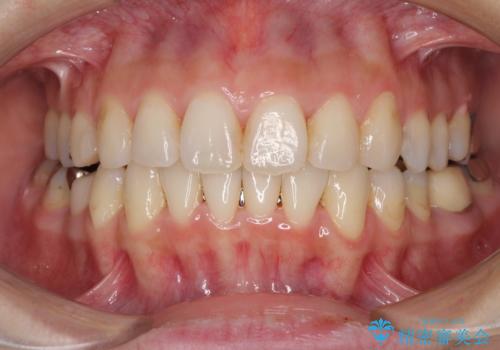

- 上下のデコボコと奥歯の咬みにくさを気にして来院された患者様です。

上顎骨の幅が下顎骨よりも小さいので、拡大装置により骨幅を広げて上下関係を改善し、その後インビザラインにて歯並びを整えることとしました。

上下の骨幅を改善したことで、スムーズに歯列矯正を行うことができました。

矯正治療中に近医で銀歯を外す治療を開始したため、治療後に奥歯の咬み合わせが不十分ですが(こちらは近医での治療により改善するとのこと)、歯列と咬み合わせが改善され、患者様には大変満足していただきました。